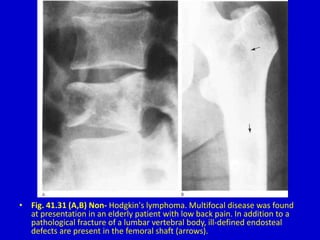

• Fig. 41.31 (A,B) Non- Hodgkin's lymphoma. Multifocal disease was found

at presentation in an elderly patient with low back pain. In addition to a

pathological fracture of a lumbar vertebral body, ill-defined endosteal

defects are present in the femoral shaft (arrows).

• Fig. 41.31(A,B) Non- Hodgkin's lymphoma. Multifocal disease was found at presentation in an elderly patient with low back pain. In addition to a pathological fracture of a lumbar vertebral body, ill-defined endosteal defects are present in the femoral shaft (arrows).